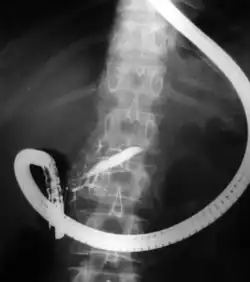

Fluoroscopic image of common bile duct stone seen at the time of ERCP. The stone is impacted in the distal common bile duct. A nasobiliary tube has been inserted.